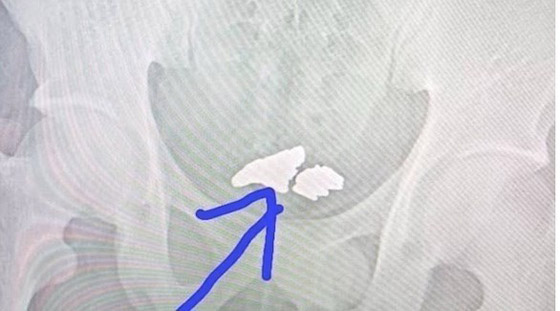

ونشرت صورة أخذت بالأشعة السينية على مواقع التواصل الاجتماعي، تُظهر قطع الذهب في الجهاز الهضمي للرجل. وسارع مستخدمو وسائل التواصل الاجتماعي للتعليق على القصة، حيث تعاطف البعض معه وقالوا بأنه موظف ولا يحصل على راتب كافٍ، في حين قال آخرون إن محاولة الرجل كانت ذكية ولكنها فشلت.

وبعد اكتشافه، تم نقل الرجل إلى المستشفى، حيث أجري له فحص بالموجات فوق الصوتية، وتبين بأن الذهب استقر في معدته، مما دفع الأطباء لإعطائه مادة خاصة مُسهلة لاستخراج الذهب.